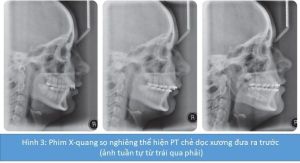

- Chẻ dọc xương trượt ra trước